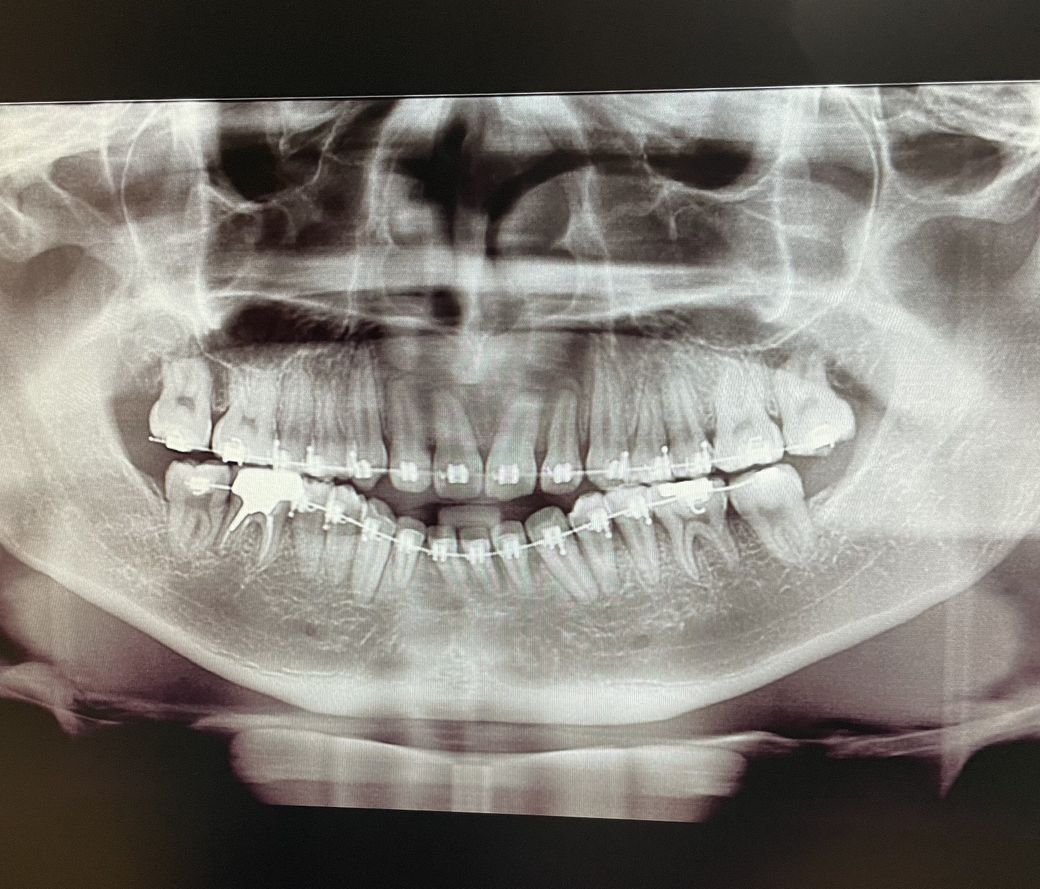

부정교합3급 오픈바이트 교정으로 해결될까요???

압구정 교정치과에서 2년동안 치료받았는데

아직도 class3 에 openbite 입니다

그치과에선 교정이 거의 마무리된상태이고 양악수술 하라고 하던데 양악은 너무 부담되어

교정으로 최대한 해결하고싶어요ㅠㅠ

그러나 전치부 치아흡수가 너무 심해 추가적인 교정이 가능할지 의문이에오ㅠㅠㅠ

단순히 파노라마 사진으로는 정확한 판단이 불가능합니다. 파노라마 사진은 3차원적인 구조물을 2차원으로 표현하기 때문에 왜곡이 상당히 심합니다. 따라서 지금으로서는 ceph. 자료와 임상 사진 등이 필요합니다. 다만 파노라마 사진 상에서도 openbite가 매우 심하다면 교정으로는 더 이상 진행하기 힘들고 아시는 것처럼 하악 전치부의 뿌리가 짧아 더 이상 교정 진행도 어려울 수 있어 보입니다. 대학 병원 방문 후 양악 수술을 할 수 밖에 없어 보입니다.

2차원적 영상인 파노라마 방사선 사진만으로는 현재 안모나 치열 등에 대한 정보를 알 수 없기 때문에 정확한 판단을 할 수 없습니다.

치료전과 현재의 치열 및 안모에 대한 3차원적인 정보 등이 있어야 정확한 판단이 가능합니다.

때문에 수술로 해결을 해야만 하는 상황인지, 단순히 교정으로 해결이 되는 상황인지를 판단하기에는 무리가 있습니다.

일단 파노라마 사진만으로는 정확한 답변이 불가능합니다.

만약 해당 치과에서 골격적 문제로 인해 수술을 권유할 정도였다면 아마도 수술외에 방법이 없을 정도로 심한 상황으로 보입니다.